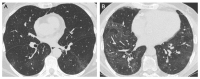

Methods: A total of 44 consecutive patients (M: 32, F: 12, average age: 64), hospitalised in our department from April to September 2020 for SARS-CoV-2-related ARDS, who had a postdischarge CT scan, were enrolled into this retrospective study. We reviewed the electronic medical charts to collect laboratory, clinical, and demographic data. The CT findings were evaluated and classified according to lung segmental distribution. The imaging findings were correlated with spirometry results and included ground glass opacities (GGOs), consolidations, reticulations, bronchiectasis/bronchiolectasis, linear bands, and loss of pulmonary volume.

Results: Alterations in the pulmonary parenchyma were observed in 97.7% of patients at HRCT (median time lapse between ARDS diagnosis and HRCT: 2.8 months, range 0.9 to 6.7). The most common findings were linear bands (84%), followed by GGOs (75%), reticulations (34%), bronchiolectasis (32%), consolidations (30%), bronchiectasis (30%) and volume loss (25%). They had a symmetric distribution, and both lower lobes were the most affected areas.

Conclusions: A reticular pattern with a posterior distribution was observed 3 months after discharge from severe COVID-19 pneumonia, and this differs from previously described postCOVID-19 fibrotic-like changes. We hypothesized that the systematic use of prolonged low-dose of corticosteroid could be the main reason of this different CT scan appearance.